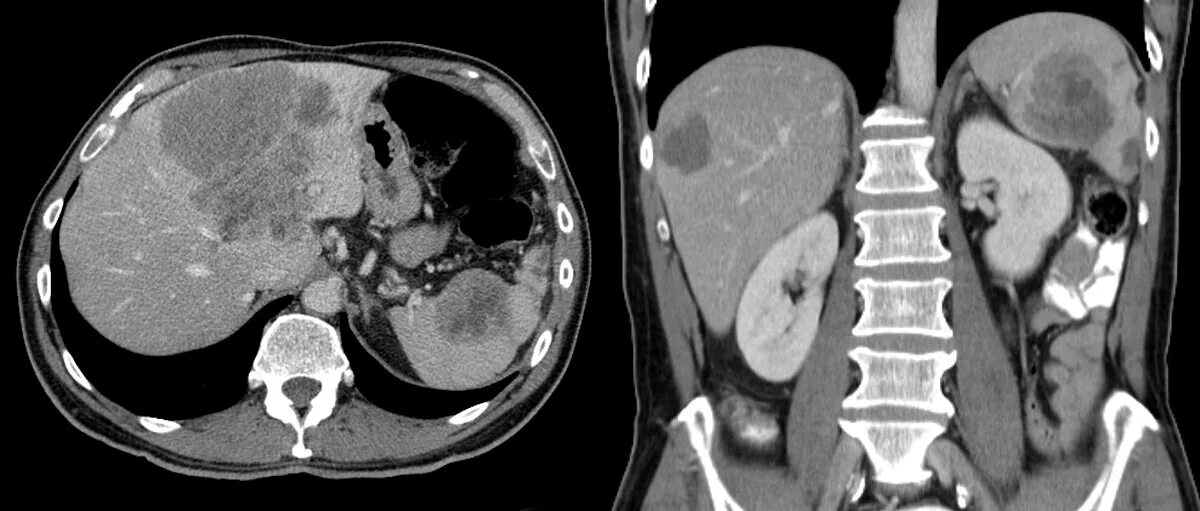

Метастазы 3 стадии